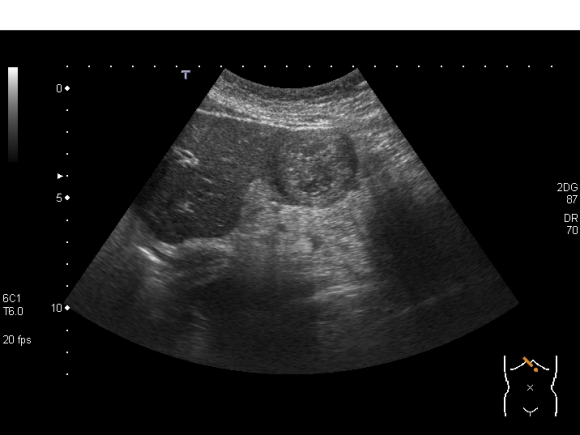

EMA症例36:1月症例 38歳女性 - 嘔気。病歴が大切。

【症例】38歳女性

【主訴】嘔気

ADL自立した中肉中背女性。配偶者、子供と生活している。来院日当日の朝から嘔気を自覚していた。嘔吐はしていない。昼になり心窩部痛も出現して来たために救急外来を独歩受診。目眩や耳鳴、難聴はない。頭痛無し。下痢なし。海外旅行なし。生もの摂取は最近していない。周囲に胃腸炎の人はいない。

これまでにも1ヶ月に一度程度の頻度で、嘔吐下痢を来すことがあり、たびたび病院受診をしていた。受診回数は20回を超えている。これまでは胃腸炎と言われており、今回の嘔気と心窩部痛はその時の症状と同じである。